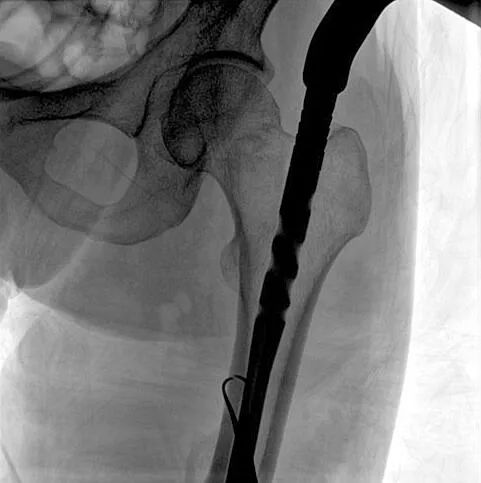

患者:男性,43歲,左股骨干骨折髓內(nèi)釘內(nèi)固定術

C形臂輔助手術過程

術中使用普愛醫(yī)療大平板一體式C形臂進行透視,判斷骨折情況及克氏針、髓內(nèi)釘?shù)冉饘僦踩胛锏奈恢茫M行調(diào)整。C形臂準確的術中定位,大大縮短了手術的時間,減輕了患者的痛苦,輔助手術順利完成。

在進行髓內(nèi)釘內(nèi)固定術時,醫(yī)生需要同時觀察到入釘點和骨折部位的情況,普愛醫(yī)療大平板一體式C形臂采用30CM×30CM的平板探測器,能夠呈現(xiàn)更廣闊的成像面積,滿足大部分長骨髓內(nèi)釘內(nèi)固定術的攝片需求。

術中定位準確、出血量少,術后影像顯示股骨移位糾正,恢復良好力線,手術效果良好。